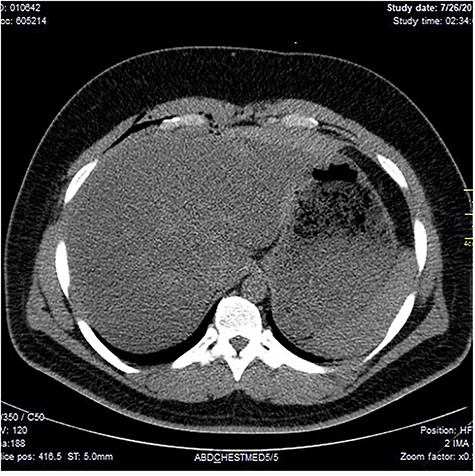

Chest X-ray was normal as shown in Fig. 1. Focused abdominal sonography for trauma (FAST) scan showed mild left perihepatic collection necessitating a thoracoabdominal computerized tomography (CT)-scan which showed external oblique muscle laceration with intermuscular air lucencies and grade 2 hepatic injury as shown in Figs 2–4. Other blood work-up were normal. No other injury was found on secondary survey. His wound was explored under local anaesthesia, primarily repaired, and he was discharged after 24 h of close observation.

Showing lucent air densities tracking through the right intercostal muscles and abutting on the liver in the epigastrum with associated subcapsular haematoma in the left lobe of the liver.